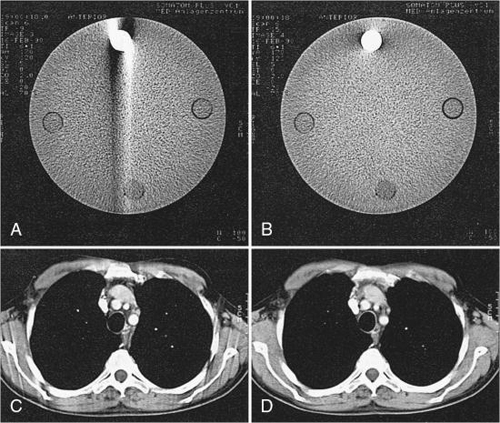

Inconsistent data obtained from 360-degree spiral/helical scan rotation are used directly in the image reconstruction process. Motion artifacts are apparent as shown in Fig. 12.12, for phantom images, and in Fig. 12.13, for patient images.